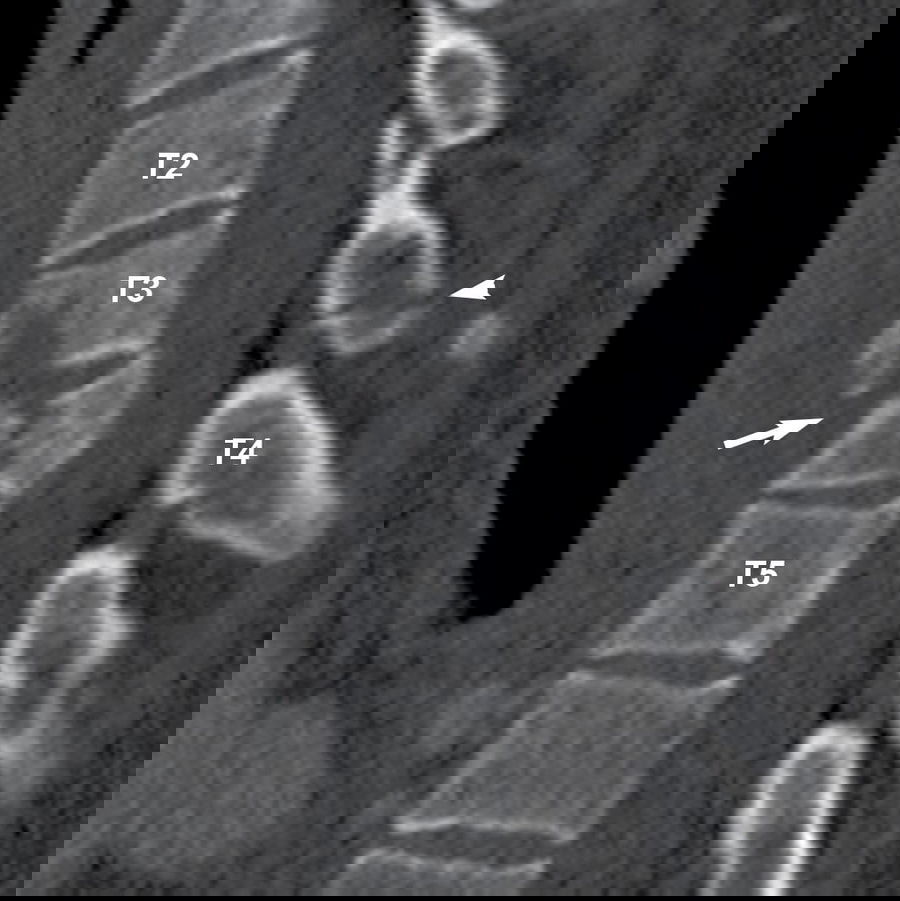

There are 12 vertebrae that make up the thoracic spine, and they are labeled T1 through T12. Located between the cervical and lumbar regions of the spine, it serves as the body’s structural and functional hub. The thoracic spine consists of 12 vertebrae that attach directly to the rib cage.

article-image

T3 is the third cervical vertebra down the spine, between T2 and T4. The T3 vertebra acts as a master switch for the chest muscles and, subsequently, the lungs and bronchial tubes. Following any T3 vertebra injury, symptoms include difficulty breathing, asthma, cough, and illnesses including bronchitis, influenza, and pneumonia. The severity of the injury and the patient’s survival depends on the extent of the spinal cord damage.